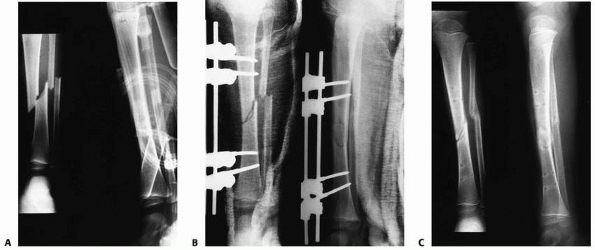

FIGURE 25-8 Developmental valgus after a proximal tibial metaphyseal fracture and subsequent corrective osteotomy. A.

Radiograph taken 6 months after a fracture of the proximal tibia. The injury was nondisplaced. The scar from the initial proximal metaphyseal fracture is still seen (arrow). This child developed a moderate valgus deformity of the tibia within 6 months of fracture. B. A proximal tibial corrective osteotomy was performed. C. Two months postoperatively, the osteotomy was healed and the deformity corrected. D. Five months later, there was a recurrent valgus deformity of 13 degrees. (Courtesy of John J.J. Gugenheim, MD.) |

![]() |

|

FIGURE 25-9 A. Anteroposterior image of a Salter-Harris type II fracture of the proximal tibia. Notice the valgus alignment. B. This fracture was treated with percutaneous pin fixation after reduction. C. This patient developed tibia valga over a period of approximately 2 years following the injury. D. A medial proximal tibial hemiepiphysiodesis using a staple was performed.